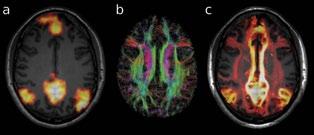

division heads division heads

Professor Alan Connelly is an NHMRC Principal Research Fellow. He is the Co-Division Head of the Imaging Division, and Head of the Advanced MRI Development group. He also heads the MRI imaging Facility at the Florey Austin (including two researchonly 3T MRI scanners) and the Florey Parkville Small Animal Imaging Facility. Prof Connelly is a development MRI physicist whose work has encompassed a range of MR methods, with current focus primarily on diffusion and perfusion MRI and their application to the investigation of epilepsy, stroke, and cognitive function. His group is internationally recognised as leaders in the field of diffusion MRI fibre tractography, and has developed novel methods to characterise the complex white matter fibre connections in the brain. He has published widely in magnetic resonance, general scientific, and neuroscientific journals, and is a member of the editorial board of Epilepsia.